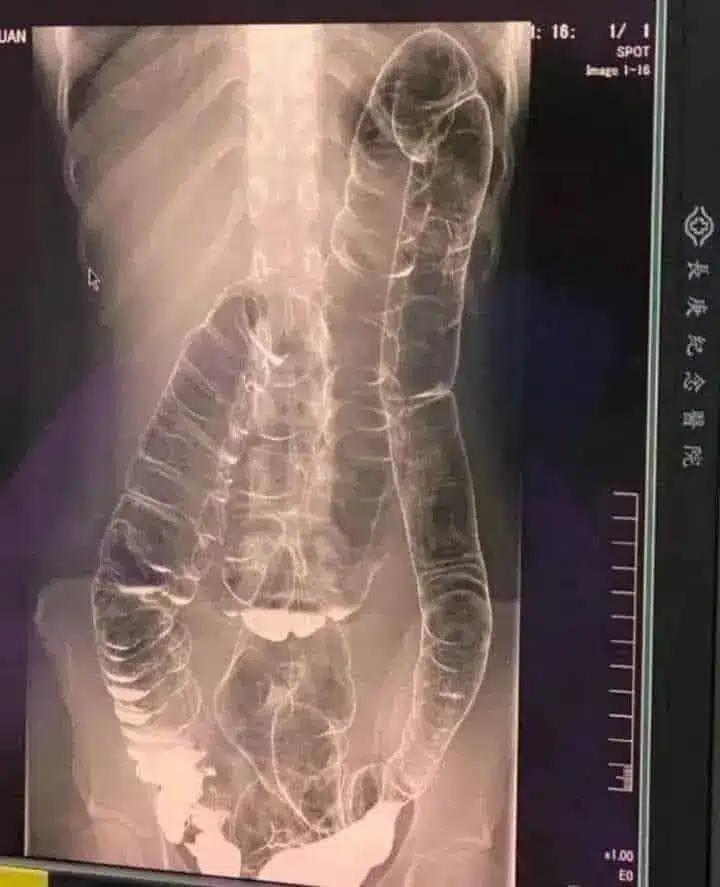

Συγκλονιστική ακτινογραφία ασθενούς με μακροχρόνια δυσκοιλιότητα

Η παρακάτω εικόνα με ακτίνες Χ ανήκει σε μια νεαρή γυναίκα που έπασχε από χρόνια δυσκοιλιότητα για χρόνια. Μια μέρα, η κατάστασή της επιδεινώθηκε και έμεινε για πάνω από δύο εβδομάδες χωρίς κένωση. Αναζήτησε τελικά ιατρική βοήθεια, αλλά τα αποτελέσματα ήταν ανησυχητικά .

Στην ακτινογραφία, μπορείτε να δείτε πώς το κόλον έχει επεκταθεί δραματικά, φτάνοντας μέχρι την περιοχή του θώρακα, κοντά στην καρδιά.

Οι φυσιολογικές πτυχές και διπλώσεις του παχέος εντέρου, που είναι απαραίτητες για τη λειτουργία του, έχουν σχεδόν εξαφανιστεί λόγω υπερβολικού φουσκώματος και διάτασης.